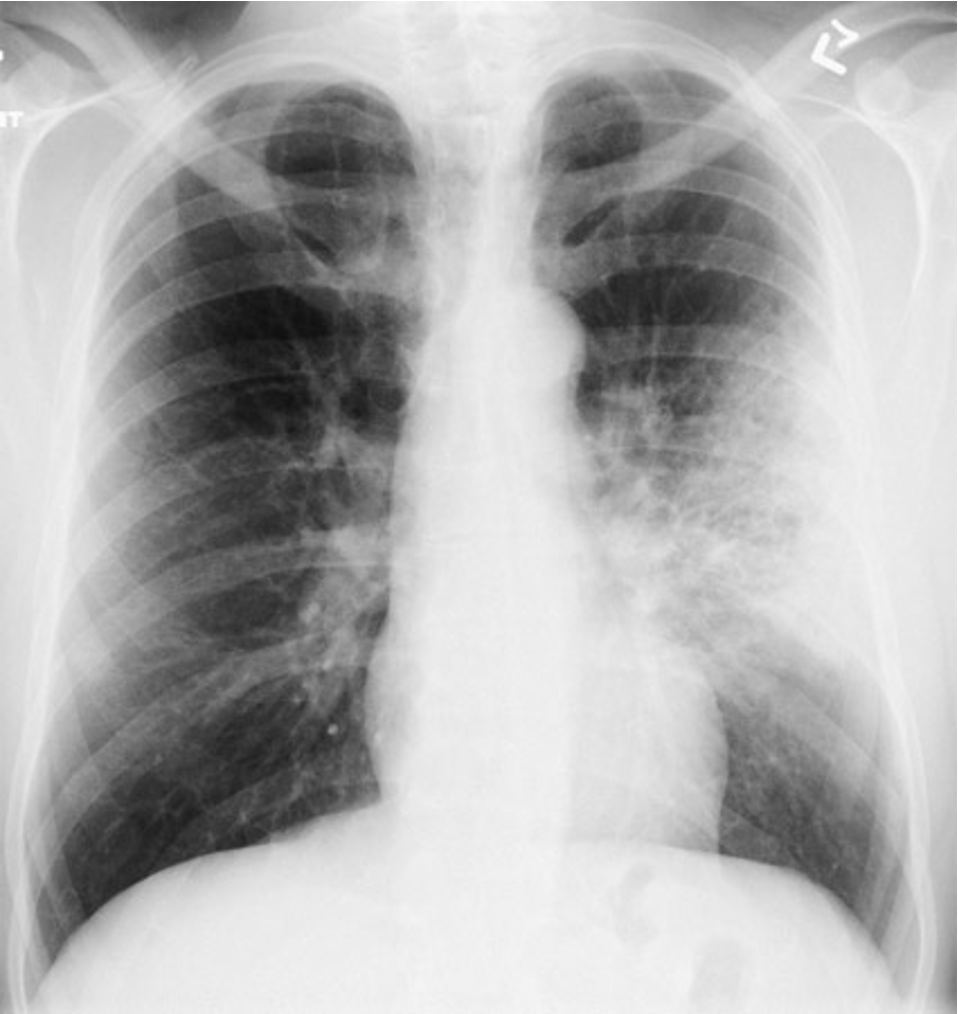

Normal CXR (PA & Lateral)